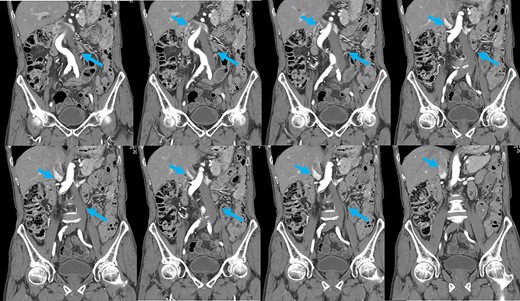

Preoperative computed tomography (CT) revealed a tumor in the sigmoid colon accompanied by some regional lymph node swelling (Fig. 1). It also showed that the IVC ascended vertically along the left side of the abdominal aorta. After connecting with the left renal veins, the left-sided IVC crossed the abdominal aorta anteriorly to join the normal prehepatic segment of the IVC (Figs 2 and 3). Coronal CT showed that the descending colon misplaced at the abdominal midline and the sigmoid colon in the right upper abdomen (Fig. 4). The preoperative diagnosis was thus sigmoid colon cancer with left-sided IVC and PDM.

Coronal reformation of the CT image shows precisely how the left-sided IVC (arrows) ascended vertically along the left side of the abdominal aorta and crossed anterior to the aorta.